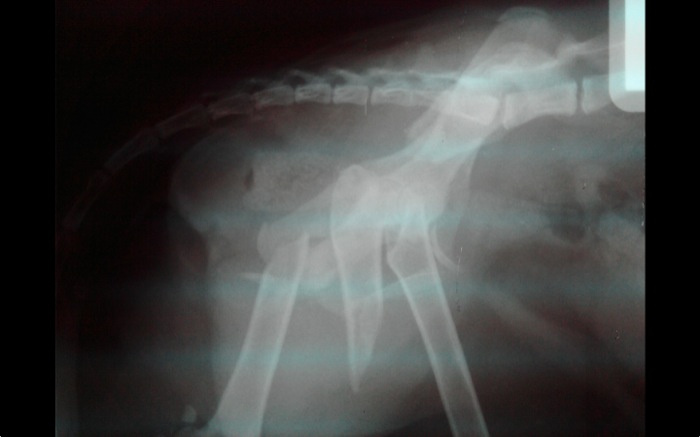

La radiografía de control es buena y el paciente se recupera también rápido de esta segunda intervención. Aunque a veces el operar en uno o dos tiempos un paciente suponga una duda normalmente se opta por esta solución cuando el estado físico es delicado como en este caso.

A los 11 días el gato se desplaza por la consulta con bastante agilidad y sin deficits neurológicos visibles. La recuperación avanza mejorando las previsiones iniciales desde el principio dado los 5 días que parece haber pasado perdido hasta llegar en estas condiciones a su casa.